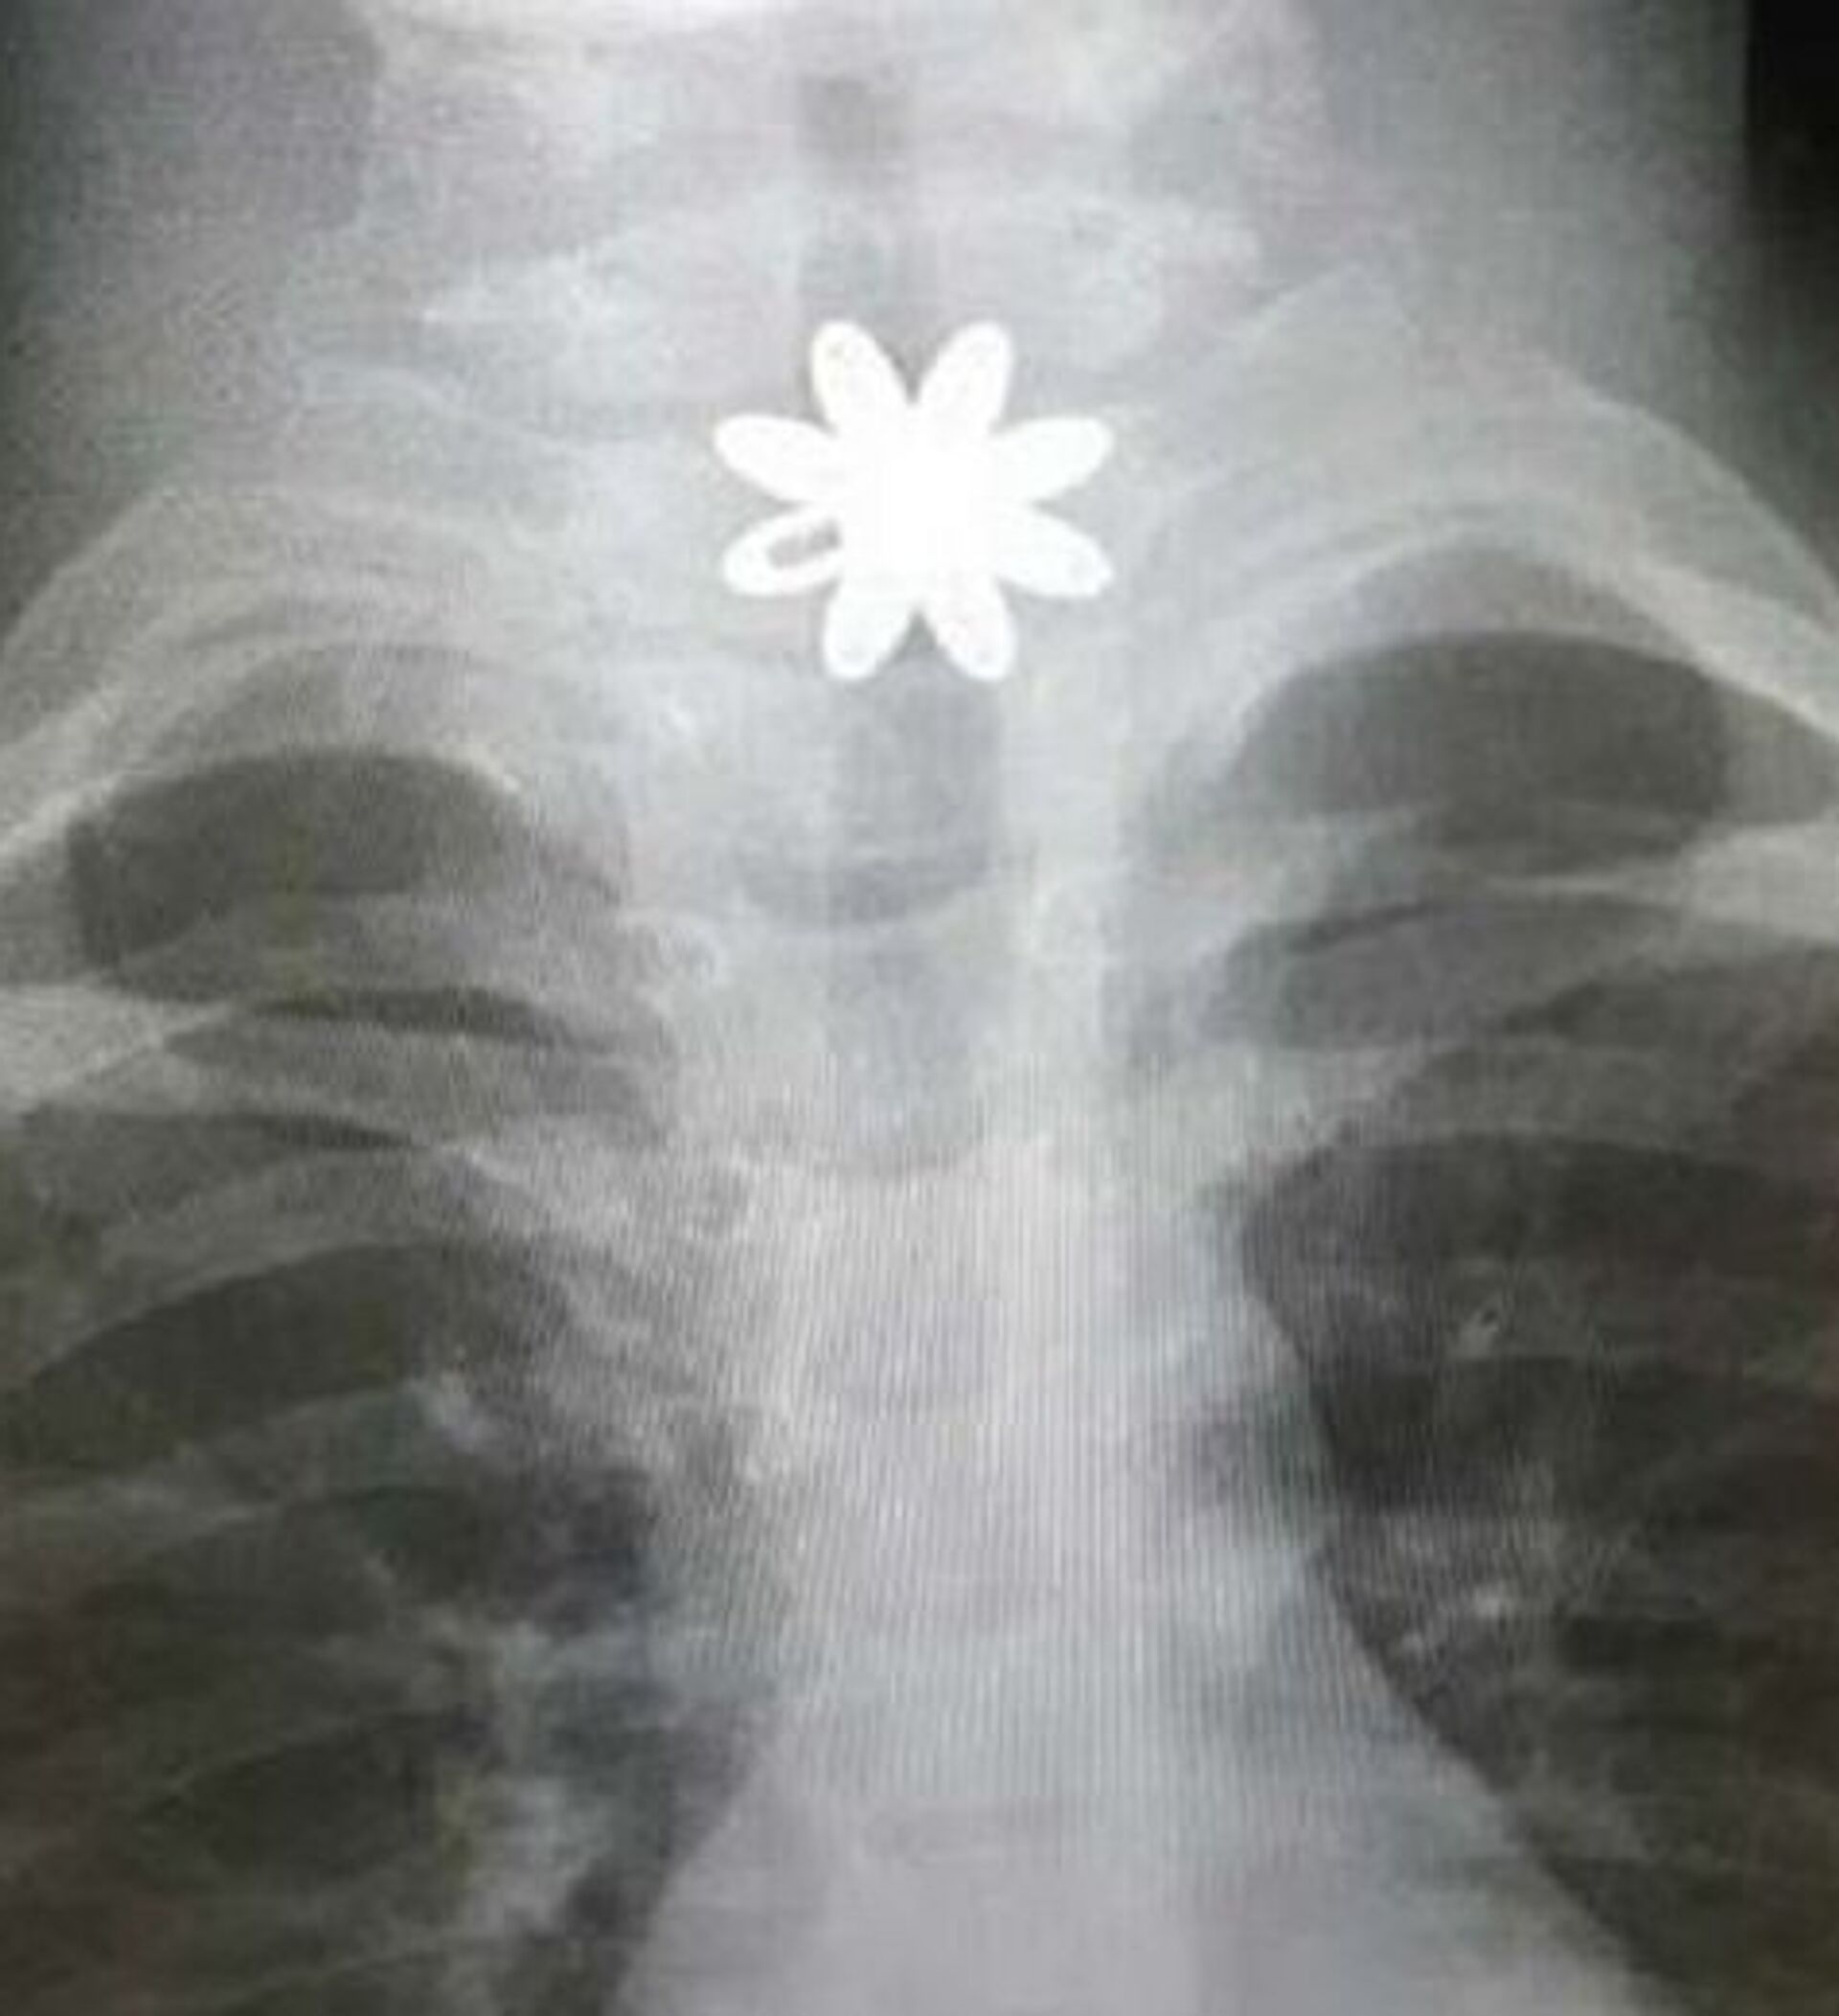

وفي التفاصيل، تم إدخال الطفلة إلى المستشفى وهي تعاني انسدادا في المريء، وبعد تشخيص الحالة، اتضح وجود قطعة معدنية حادة تشكل خطورة على حياة الطفلة، ممّا أدى إلى جروحٍ قطعية داخل المريء، بحسب "المواطن".

وخضعت الطفلة لعملية باستخدام منظار المريء الصلب، لاستخراج القطعة المعدنية، في وقت قياسي وبشكل دقيق وسريع، وتمّت معالجة الحالة، حيث غادرت المستشفى بصحةٍ جيدة.